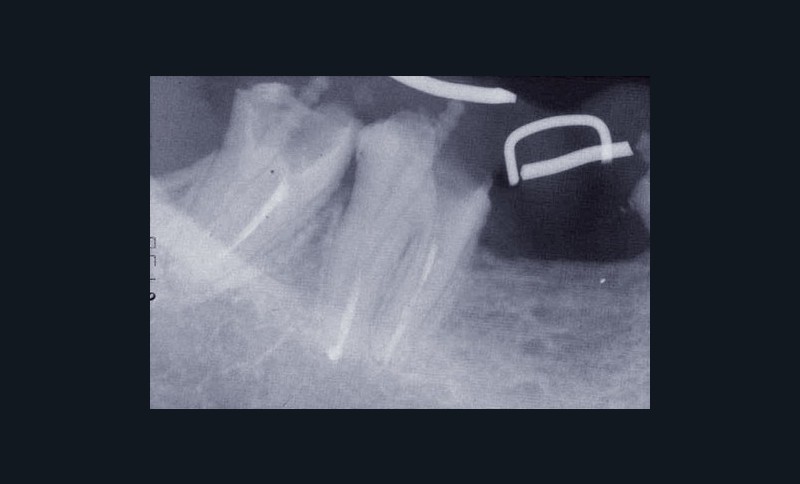

Les examens cliniques et radiographiques montrent une parodontite chronique généralisée (fig. 1a à m).